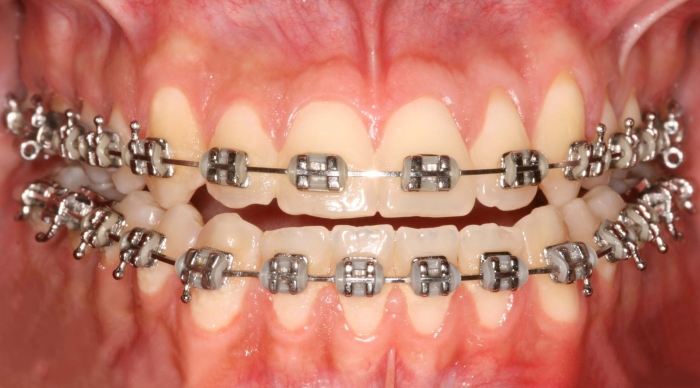

Mordida inicial